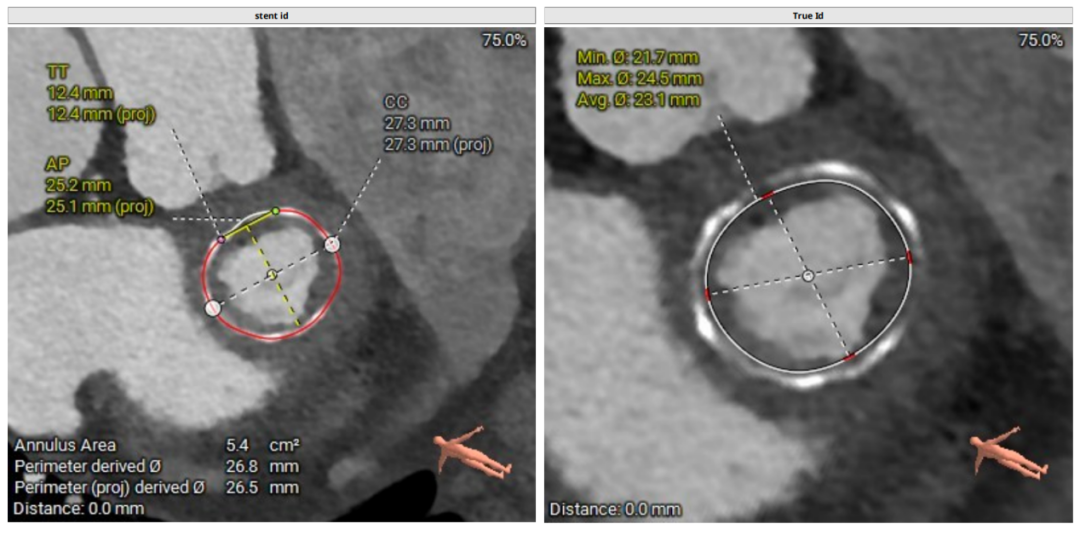

二尖瓣生物瓣支架内径 26.5mm,结合瓣架形态、瓣架高度及手术记录,符合EPIC 27#。瓣中瓣治疗考虑选择25# 介入瓣膜。模拟25# 瓣膜植入,测得NEO-LVOT 面积155.8mm²,术后存在新流出道梗阻风险。左心耳尖端未见血栓。左心房增大73.4*118.7mm,房间隔未见增厚,未见明显钙化,靠后靠下房间隔穿刺点距二尖瓣水平高度27.7mm,房间隔穿刺点高度可。